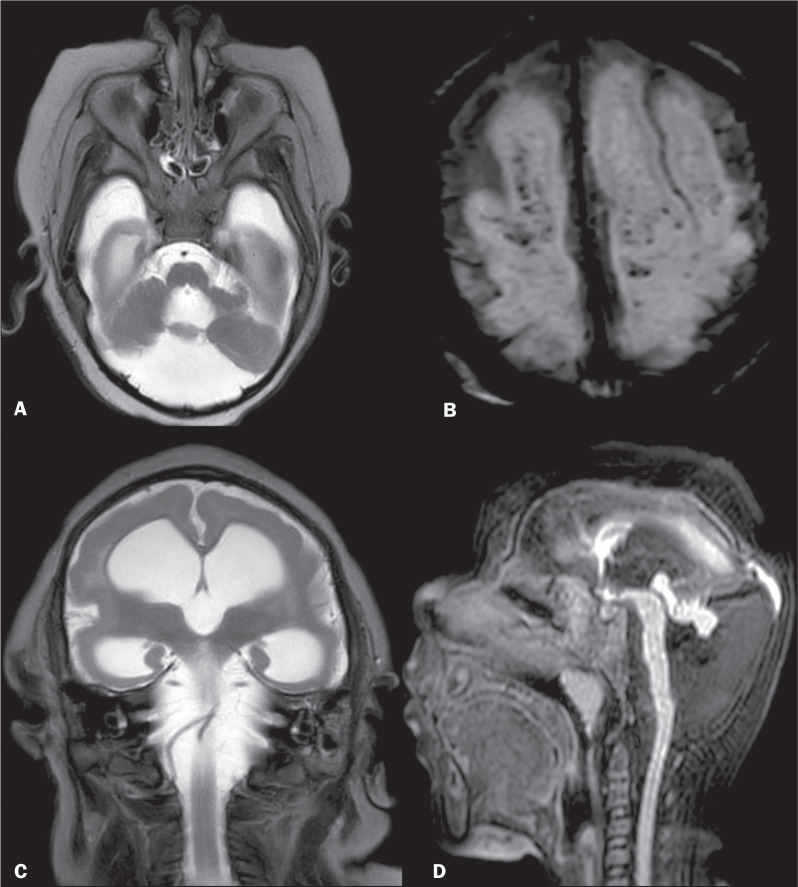

Results: The sample included 36 infants exposed to ZIKV perinatally. Therefore, a total of 72 MRI scans were evaluated. Among the 36 infants included a diagnosis of CZS was made in 25 (69.4%), of whom 18 presented with a combination of classic findings (including reduced brain volume, subcortical calcifications, brainstem hypoplasia, malformations of the corpus callosum, malformations of cortical development, and ventriculomegaly), as well as atypical findings such as hyperintense foci in the white matter on T2-weighted sequences. Of those same 25 infants, seven presented with mild lesions. Of the 11 normocephalic patients, five (13.9%) had atypical findings such as hyperintense foci in the white matter on T2-weighted sequences and no other manifestations of CZS, although there was mild neurological involvement. Six (16.6%) of the 36 patients had completely normal MRI scans with no neurological changes. No disease progression was observed during follow-up.

Conclusion: In infants exposed to ZIKV perinatally, the frequency of classic and atypical findings on brain MRI seems to be associated with the neurological status. Brain MRI is an important diagnostic tool in the evaluation and monitoring of patients with congenital infection, because intracranial changes other than microcephaly can occur.